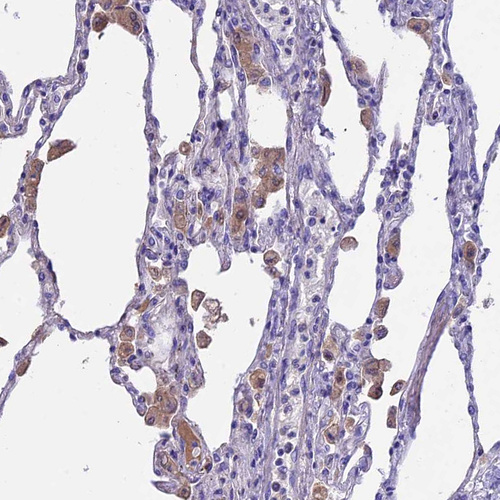

Immunohistochemical staining of human lung shows strong cytoplasmic positivity in macrophages.